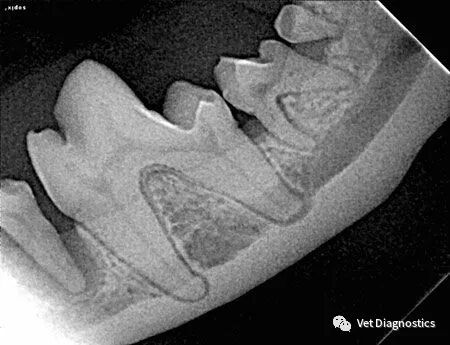

从牙冠上刮除牙菌斑和牙石,并探测牙槽,仅此而已。患者至少有60%的牙齿位于牙龈线以下。口腔内放射照片对于帮助您评估这些区域至关重要(图3A-3D)。

图3.图3A中犬科患者的晚期牙周病影响右上颌第四前磨牙和第一、第二磨牙的根尖;提示拔牙。